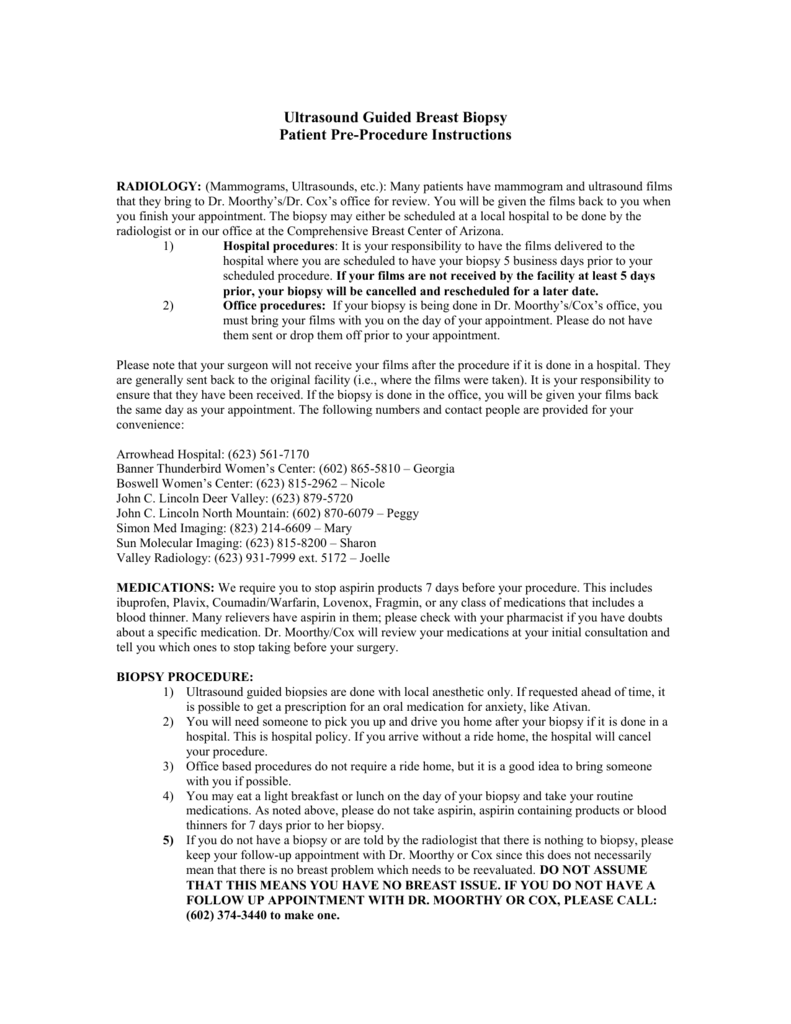

Ultrasound Guided Breast Biopsy Comprehensive Breast Center Of